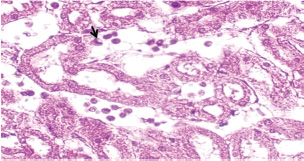

At 21 days post-infection, the lungs display moderate venous dilation and congestion, with abnormal leukocytes, indicating ongoing vascular compromise (Fig. 9). The liver showed necrotic changes in the fibrous capsule region, focal inflammatory cell infiltration, and intact hepatic cords, indicating sustained but localized damage (Fig. 10). The spleen exhibited plasma cell and macrophage proliferation within the red pulp, mild sinus dilation, and a few megakaryocytes, suggesting chronic immune activation (Fig. 11). The kidneys showed atrophic glomerular tufts and cystic dilation of adjacent tubules, indicating worsening renal pathology (Fig. 12). The mesenteric lymph nodes showed lymphoid follicles containing abnormal plasma cells and macrophages within the necrotic foci (Fig. 13).

Fig. 12. A histopathological section of the kidney (G2) at 21 days postinfection showing evidence of an atrophic tuft of many glomeruli recorded with cystic dilation of adjacent tubules (H&E stain X10).